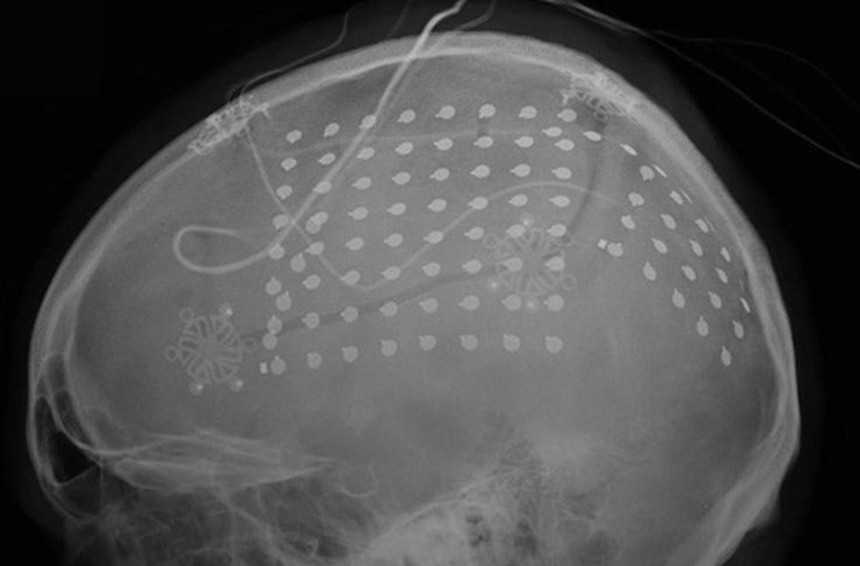

そこで研究チームは、皮質脳波検査(ECoG)を用いて、ニューロンの電気活動を記録した。これは数百もの小さな電極を皮質に設置し、脳波検査以上の空間描写とfMRI以上の解像度を得る方法だ。

皮質脳波検査には一般には推奨できないリスクがあるが、てんかんの手術ではこれによって患者の脳の活動を把握する。今回の研究はこのチャンスを活かして、いくつか実験を行なったものだ。